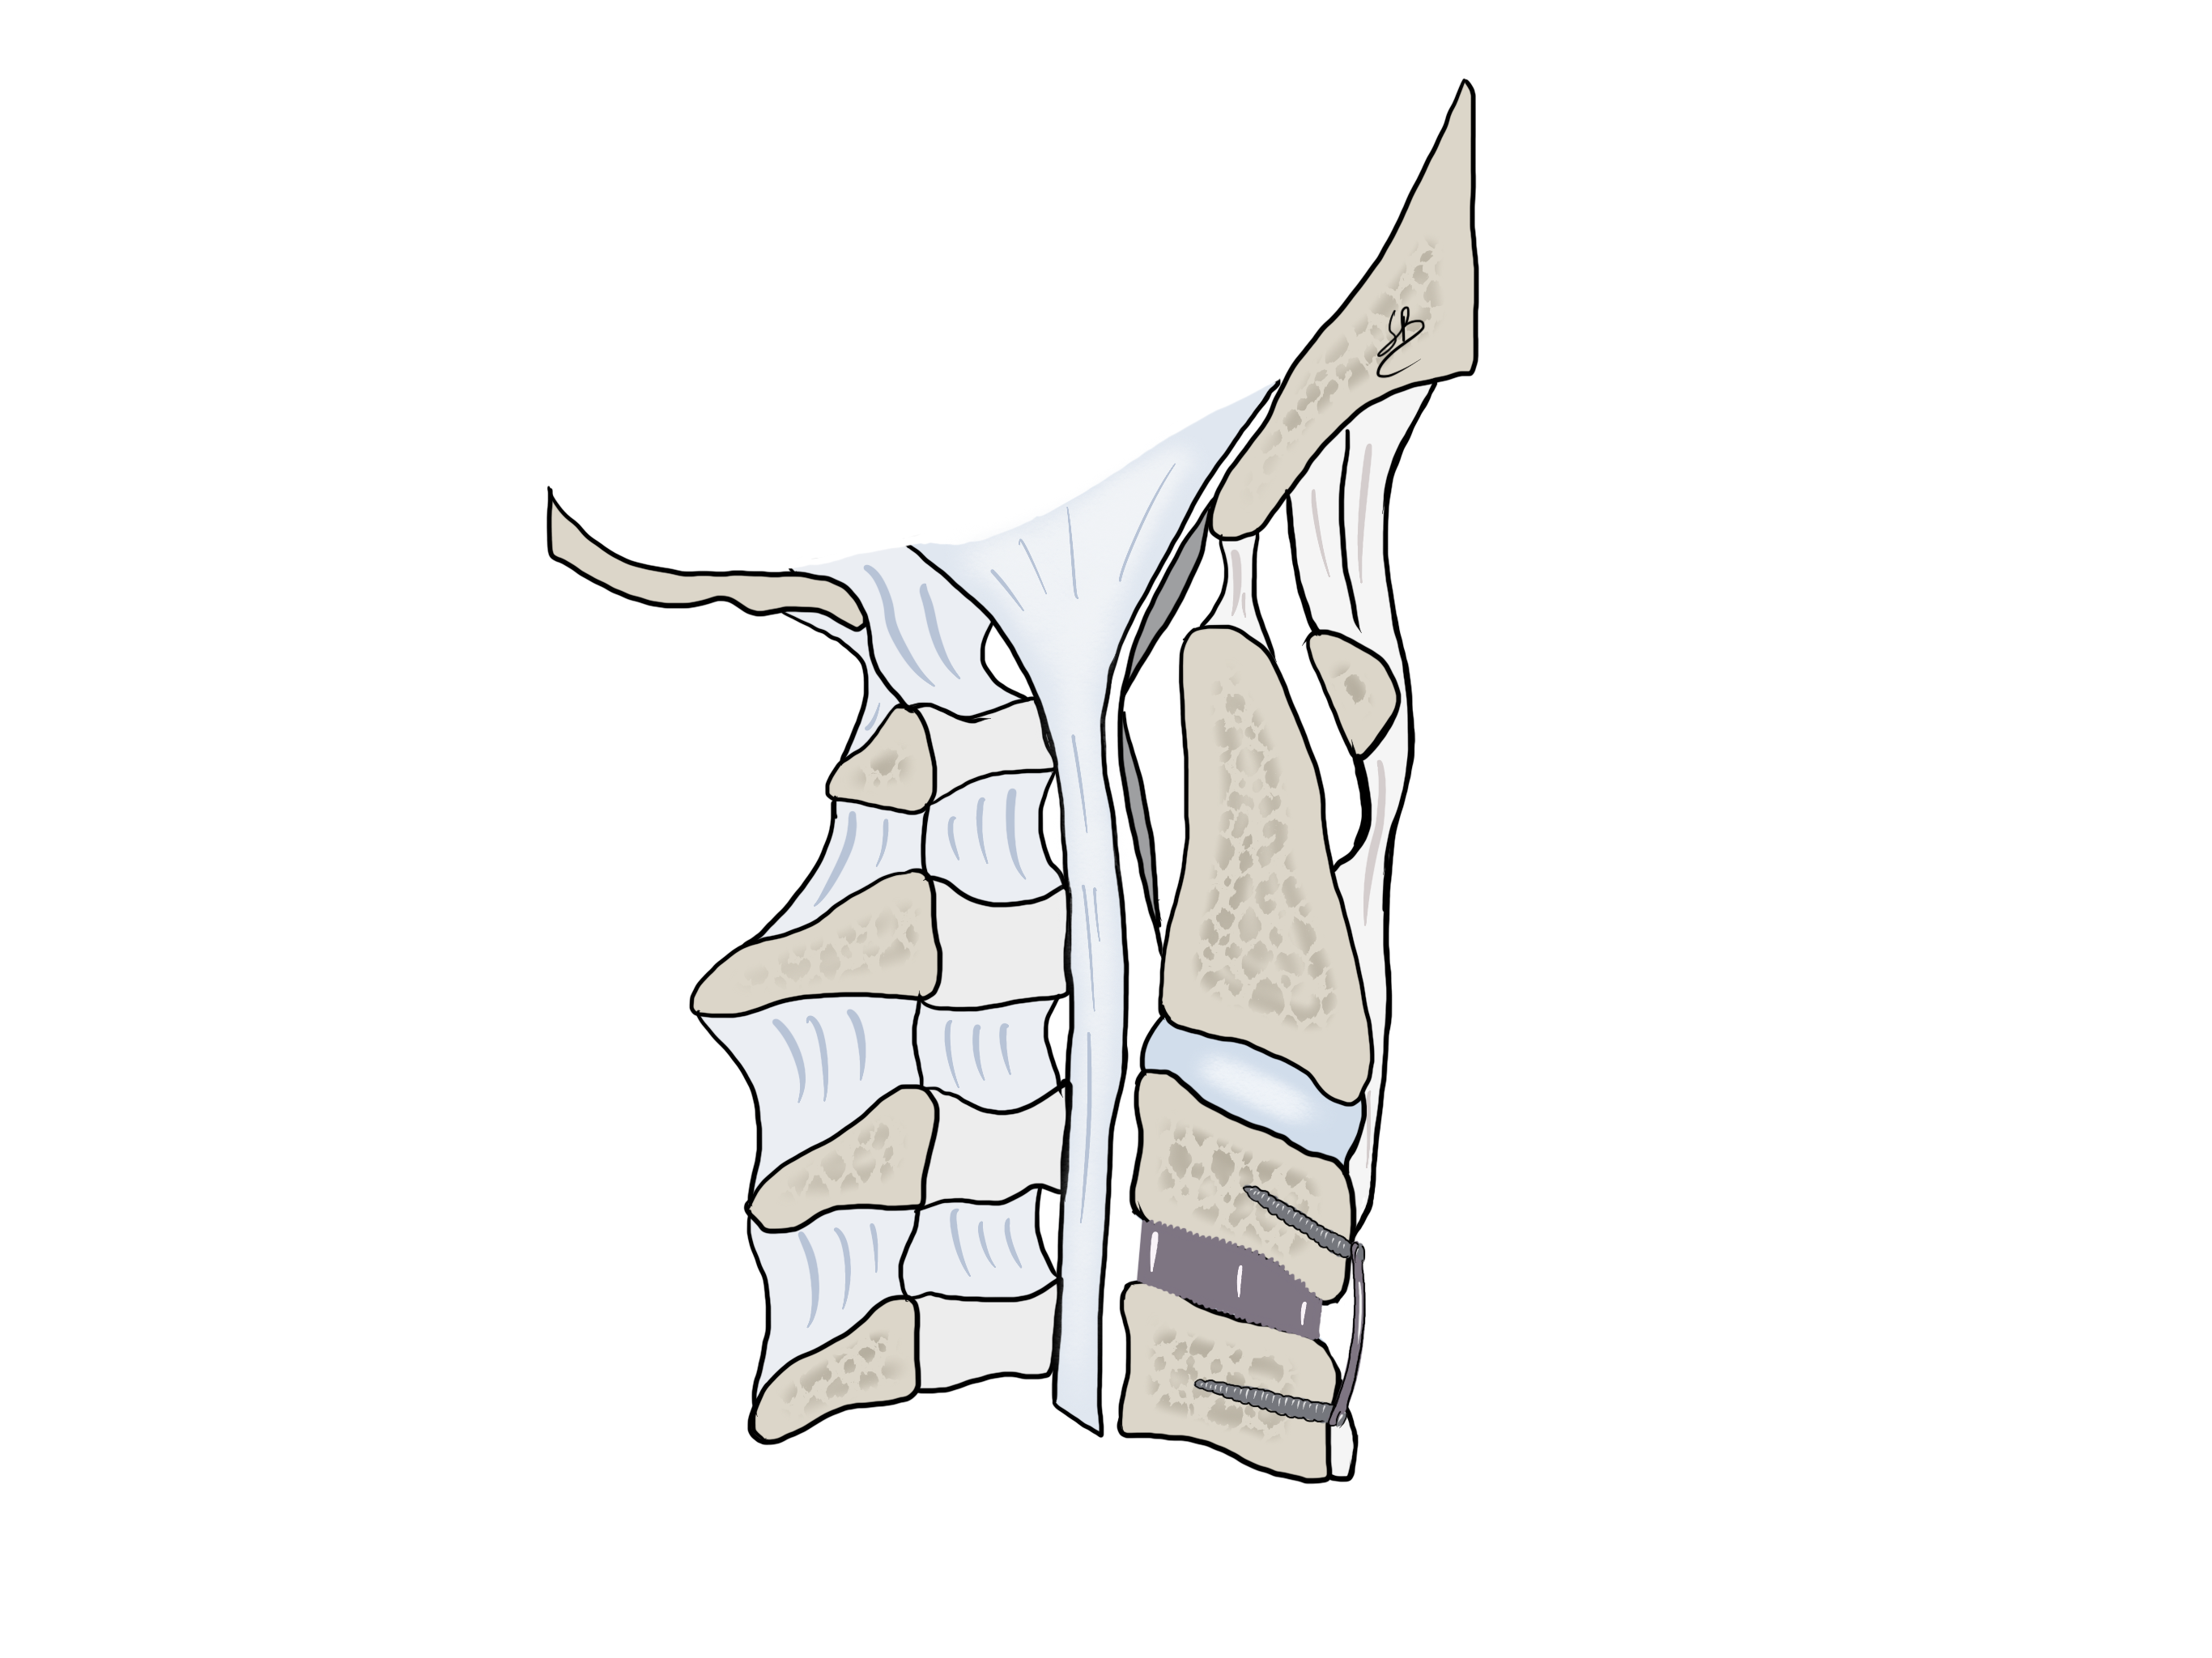

Si les méthodes conservatives ne portent aucun bénéfice, l’intervention chirurgicale devient indiquée. Il s’agit alors d’une décompression du nerf en retirant la hernie discale par voie antérieure. Le disque malade est alors substitué par une petite cage en titane. L’intervention dure environ 1 heure, sous anesthésie générale. Le Dr Robert et la Dresse Bonasia réalisent ce type d’intervention de façon microscopique pour limiter au maximum l’ouverture cutanée (environ 3 cm) ainsi que pour diminuer le risque de lésion nerveuse. Ils présentent une expérience de cette technique de plus de 200 cas opérés.

Abord cervicale anterieur par discectomie ACDF

Après un traitement chirurgical de hernie discale cervicale, le ou la patient(e) fait généralement un cycle de physiothérapie pour améliorer l’amplitudes des mouvements du cou et reprend progressivement ses habitudes quotidiennes en environ 1 mois. Nous proposons généralement un suivi ambulatoire de 1 an après ce type d’intervention.